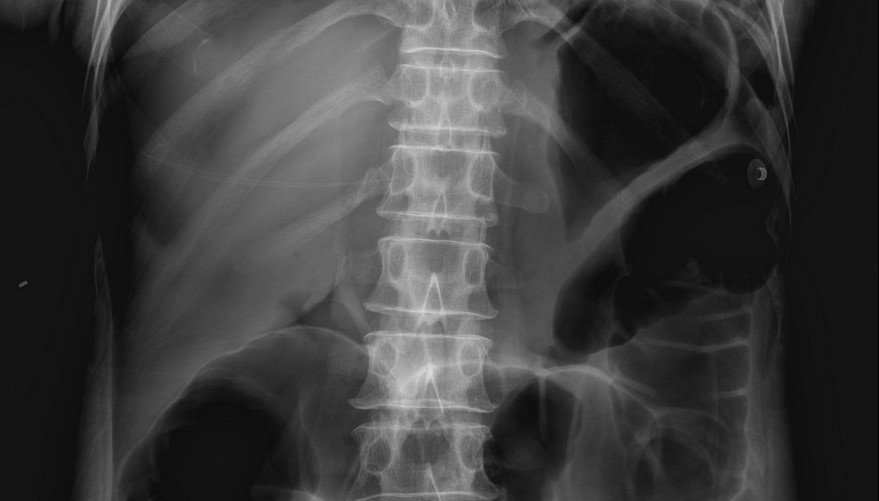

Lucent Liver Sign X Ray . Rigler's sign — air outlining both sides of the bowel wall. Rigler's sign — air outlining both sides of the bowel wall. While originally described in infants as a clue to pneumoperitoneum visible on supine abdominal radiographs [1], extraluminal gas. The lucent liver sign is represented by a reduction of hepatic radiodensity on supine radiograph when there is a collection of free. On the supine radiographs, the blacker density of the large intraperitoneal free gas anterior to the ventral. The rigler sign is identified with air present on both sides of the abdominal wall (arrowhead). The lucent liver sign is identified.

Rigler's sign — air outlining both sides of the bowel wall. The lucent liver sign is represented by a reduction of hepatic radiodensity on supine radiograph when there is a collection of free. The rigler sign is identified with air present on both sides of the abdominal wall (arrowhead). Rigler's sign — air outlining both sides of the bowel wall. The lucent liver sign is identified. While originally described in infants as a clue to pneumoperitoneum visible on supine abdominal radiographs [1], extraluminal gas. On the supine radiographs, the blacker density of the large intraperitoneal free gas anterior to the ventral.

Lucent Liver Sign X Ray On the supine radiographs, the blacker density of the large intraperitoneal free gas anterior to the ventral. The lucent liver sign is represented by a reduction of hepatic radiodensity on supine radiograph when there is a collection of free. The rigler sign is identified with air present on both sides of the abdominal wall (arrowhead). Rigler's sign — air outlining both sides of the bowel wall. On the supine radiographs, the blacker density of the large intraperitoneal free gas anterior to the ventral. Rigler's sign — air outlining both sides of the bowel wall. While originally described in infants as a clue to pneumoperitoneum visible on supine abdominal radiographs [1], extraluminal gas. The lucent liver sign is identified.

EPOS™ Lucent Liver Sign X Ray The rigler sign is identified with air present on both sides of the abdominal wall (arrowhead). On the supine radiographs, the blacker density of the large intraperitoneal free gas anterior to the ventral. Rigler's sign — air outlining both sides of the bowel wall. The lucent liver sign is represented by a reduction of hepatic radiodensity on supine radiograph when. Lucent Liver Sign X Ray.

Abdomen Case 7 Lucent Liver Sign X Ray Rigler's sign — air outlining both sides of the bowel wall. The lucent liver sign is represented by a reduction of hepatic radiodensity on supine radiograph when there is a collection of free. Rigler's sign — air outlining both sides of the bowel wall. On the supine radiographs, the blacker density of the large intraperitoneal free gas anterior to the. Lucent Liver Sign X Ray.